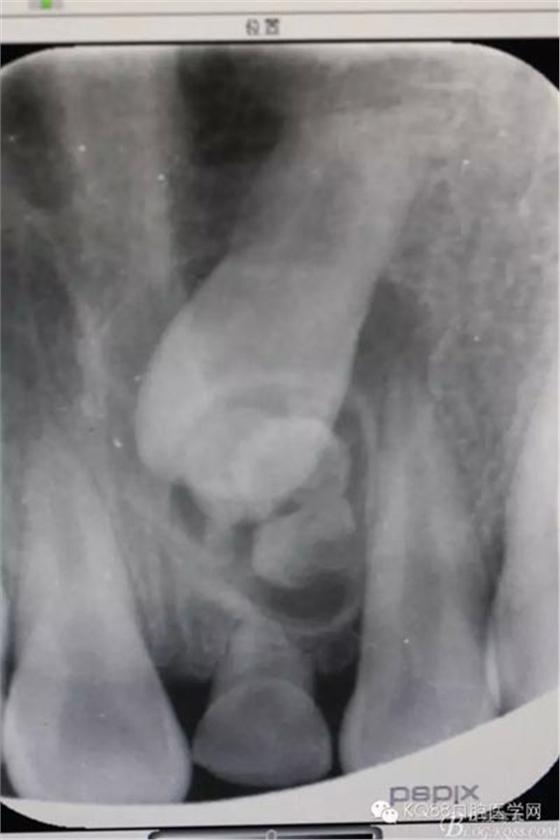

圖1.術(shù)前根尖片影像檢查:21根尖1/3彎曲,牙冠上方有一致密團(tuán)塊影。左乳Ⅰ滯留